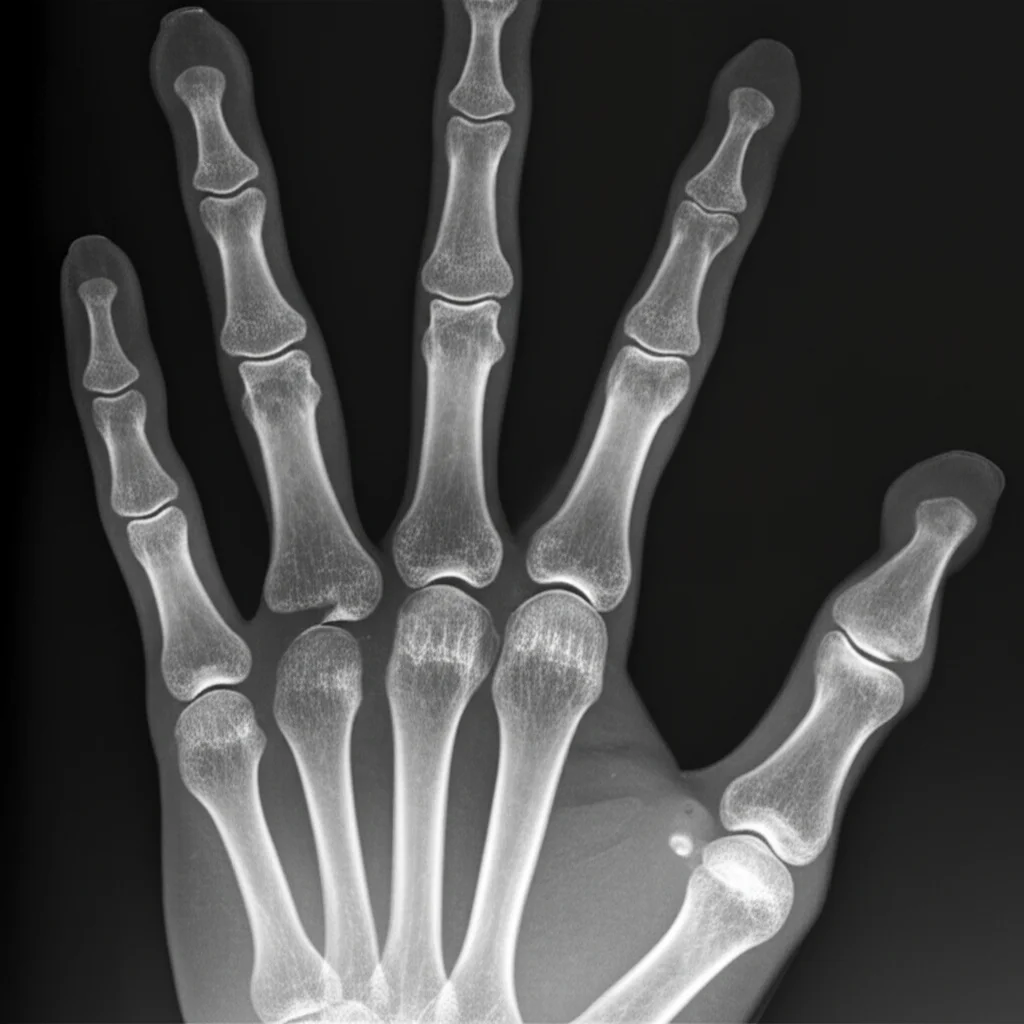

We poured over this data, looking at the morphology (what it looked like) and the radiographic findings (what the bones were doing). We also studied the existing classification systems, both for ulnar and radial (thumb side) polydactyly, particularly admiring the simplicity and logic of the Wassel classification used for radial types. We decided to base our system on the *most proximal level of skeletal involvement*. Think of it as tracing the duplication back towards the wrist – where does the extra bone (or lack thereof) start connecting or affecting the main hand structure?

In our clinical series of 64 affected hands (one patient had surgery elsewhere, so that hand’s data was incomplete), Type 0 was indeed the most common, making up 38 cases (mostly 0b and 0c). Type 4 was the next most frequent with 19 cases (mostly 4a and 4b). Types 1 and 3 were rarer, with 3 and 4 cases respectively. Importantly, our system successfully categorized all cases, including those rare Type 1b and Type 4d presentations that were difficult to fit into older systems.